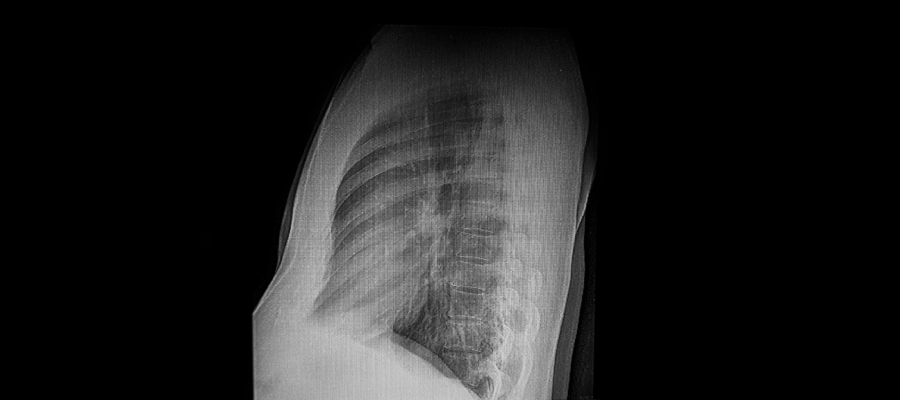

Görüntüleme Yöntemleri

Kunduracı göğsünün daha ayrıntılı şekilde değerlendirilmesine olanak tanır. Radyolojik görüntüleme (MR, BT) , deformitenin derinliği ya da kalp ile akciğerler üzerindeki etkilerini net şekilde gösterir. Bu testler, tedavi planını oluştururken önemli bir bilgi kaynağıdır.

Fizik muayene ile fark edilir ancak kesin teşhis için göğüs röntgeni, tomografi veya MR gerekebilir. Solunum fonksiyon testi ile kalp değerlendirmeleri de tanıda yardımcıdır.